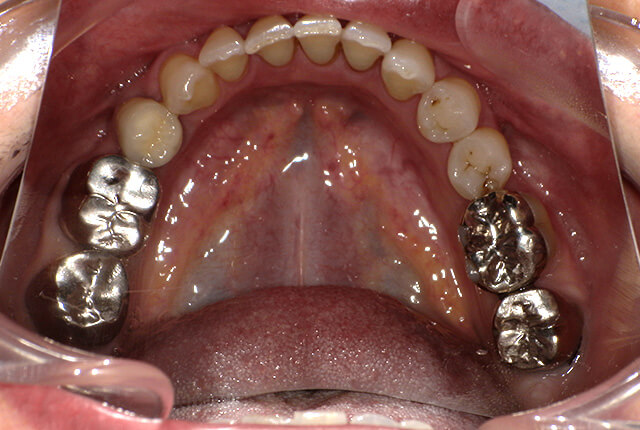

よく噛めず笑うと銀歯が目立つので気にされていました。

| 主訴 | ブリッジ脱離、しっかり噛めない |

| 診査診断 | 上顎歯牙欠損、歯周病、不良補綴、根尖性周囲炎。 不正咬合により噛み合わせのバランスが悪い事が原因により咬合治療が必要。 |

| 主訴 | 噛めない、食事がしっかりできる様になりたい。 |

| 診査診断 | 歯周病、歯の崩壊、不良補綴。 全顎的咬合異常、前歯の噛み合わせ、奥歯の噛み合わせに問題あり。 |